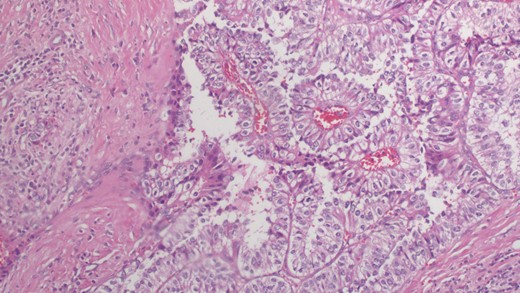

In our patient, the breast core biopsy showed multiple tiny foci of papillary proliferation with pseudo-lactational changes. However, the open biopsy showed poorly differentiated invasive ductal carcinoma with clear cell changes (Fig. 1). Ductal carcinoma in situ displays a papillary pattern with focal cystic hypersecretory (pseudo-lactating) features (Fig. 2). Microscopic examination showed that the tumor cells contained abundant fine glycogen granules in their clear cytoplasm, which were stained by a periodic acid-schiff (PAS) stain, but not stained by a diastase-PAS stain. There were features of poorly differentiated carcinoma with a prominent micropapillary growth pattern. Extensive ductal carcinoma in situ with solid, micropapillary, flat and cribriform types with an intermediate-to-high nuclear grade with necrosis was also noted. Invasive and in situ carcinomas both show clear cell and cystic hypersecretory changes. The breast core biopsy specimen showed atypical ductal hyperplasia with clear cell changes.

Microscopic examination reveals well-formed angular and papillary epithelial tumor cells with ample clear cytoplasm (×20).